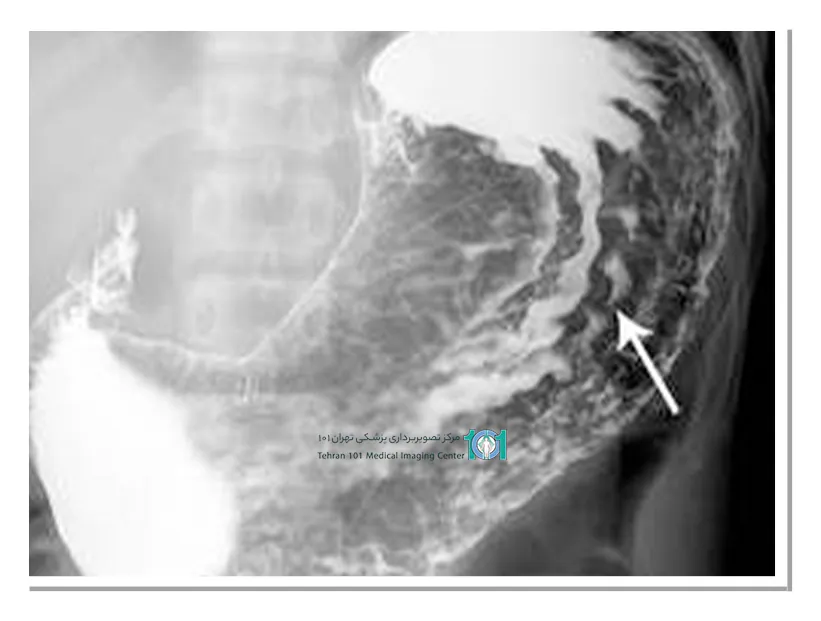

محلول طعمدار و شیرین شده است اما باز هم ممکن است طعم خوشایندی نداشته باشد. در طول آزمایش، بسته به شرایط، محلول را به مرور و به صورت جرعهجرعه مینوشید. رادیولوژیست تصویربرداری را از زوایای مختلفی انجام میدهد؛ به همین دلیل ممکن است از شما بخواهد به روشهای مختلف حرکت کنید تا با حرکت باریم تصویربرداری از تمام نواحی انجام شود.

احتمالا از شما خواسته میشود که چند حالت مختلف هم به صورت ایستاده و هم دراز کشیده بگیرید. همچنین ممکن است کمی به شکم شما فشار وارد کنند تا چینها نیز آشکار شوند.

پرتونگاری معده در چه حالتهایی انجام میشود؟

حالتهای رایج در انجام پرتونگاری معده عبارتاند از:

- ایستادن با زاویهی ۴۵ درجه

- چرخش به عقب با زاویهی ۴۵ درجه

- دراز کشیدن به صورت افقی و بر روی یک سمت بدن

- دراز کشیدن و چرخش ملایم به عقب

پرتونگاری معده آزمایشی بدون درد و غیرتهاجمی است که به پزشک شما امکان بررسی مری، معده و ابتدای رودهی شما را میدهد. فلوروسکوپی به رادیولوژیست این امکان را میدهد که اندامهای شما را در حال حرکت ببینند و نحوهی عملکرد آنها را مشاهده کنند.